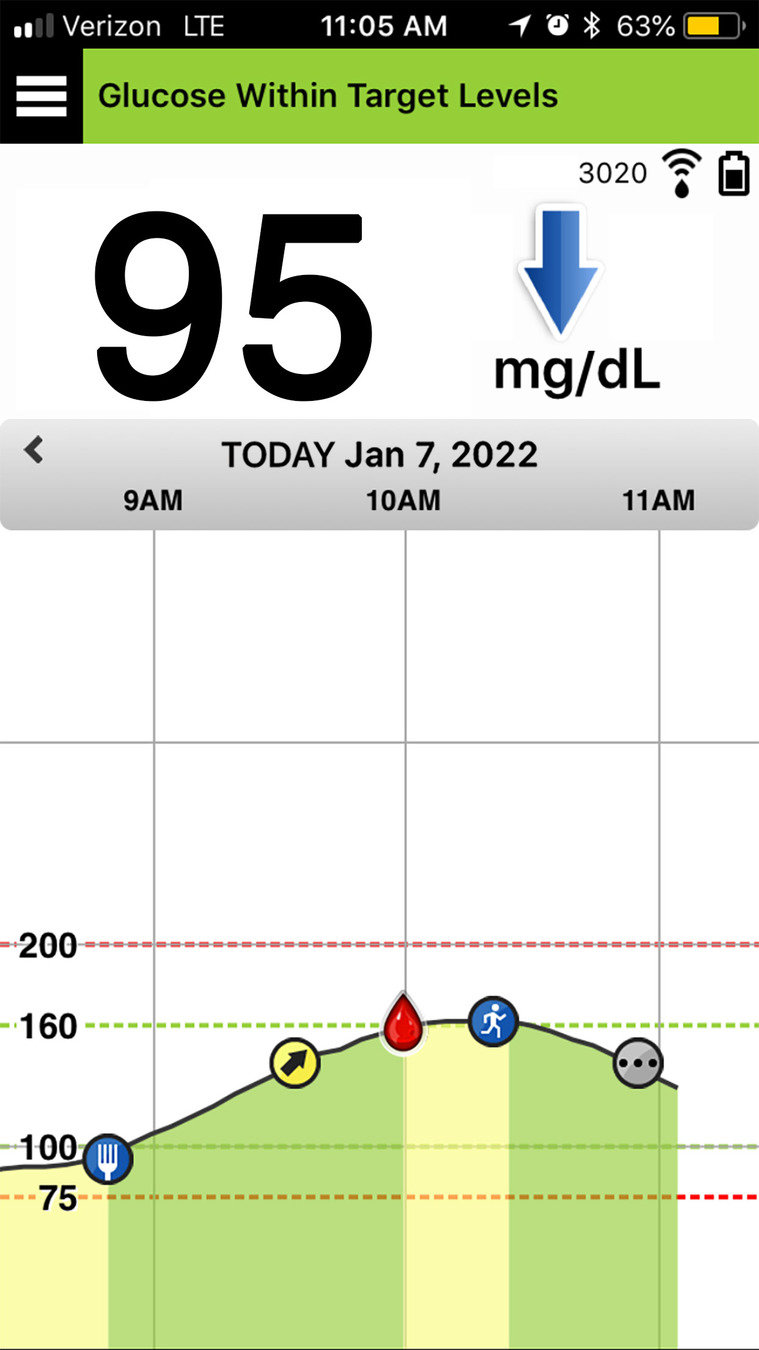

No obstante, ¿qué pasa si en su lugar observa esta situación?

Su nivel de glucosa es de 95 mg/dL, pero la flecha de tendencia apunta por completo hacia abajo. Esto quiere decir que la glucosa está disminuyendo con mucha rapidez: al menos 2 mg/dL/min. Por tanto,

el nivel de glucosa podría ser 60 puntos menor en 30 minutos. Teniendo en cuenta esta información, probablemente ajustará su dosis de insulina antes de las comidas para evitar un nivel bajo de glucosa.

FLECHAS DE TENDENCIA